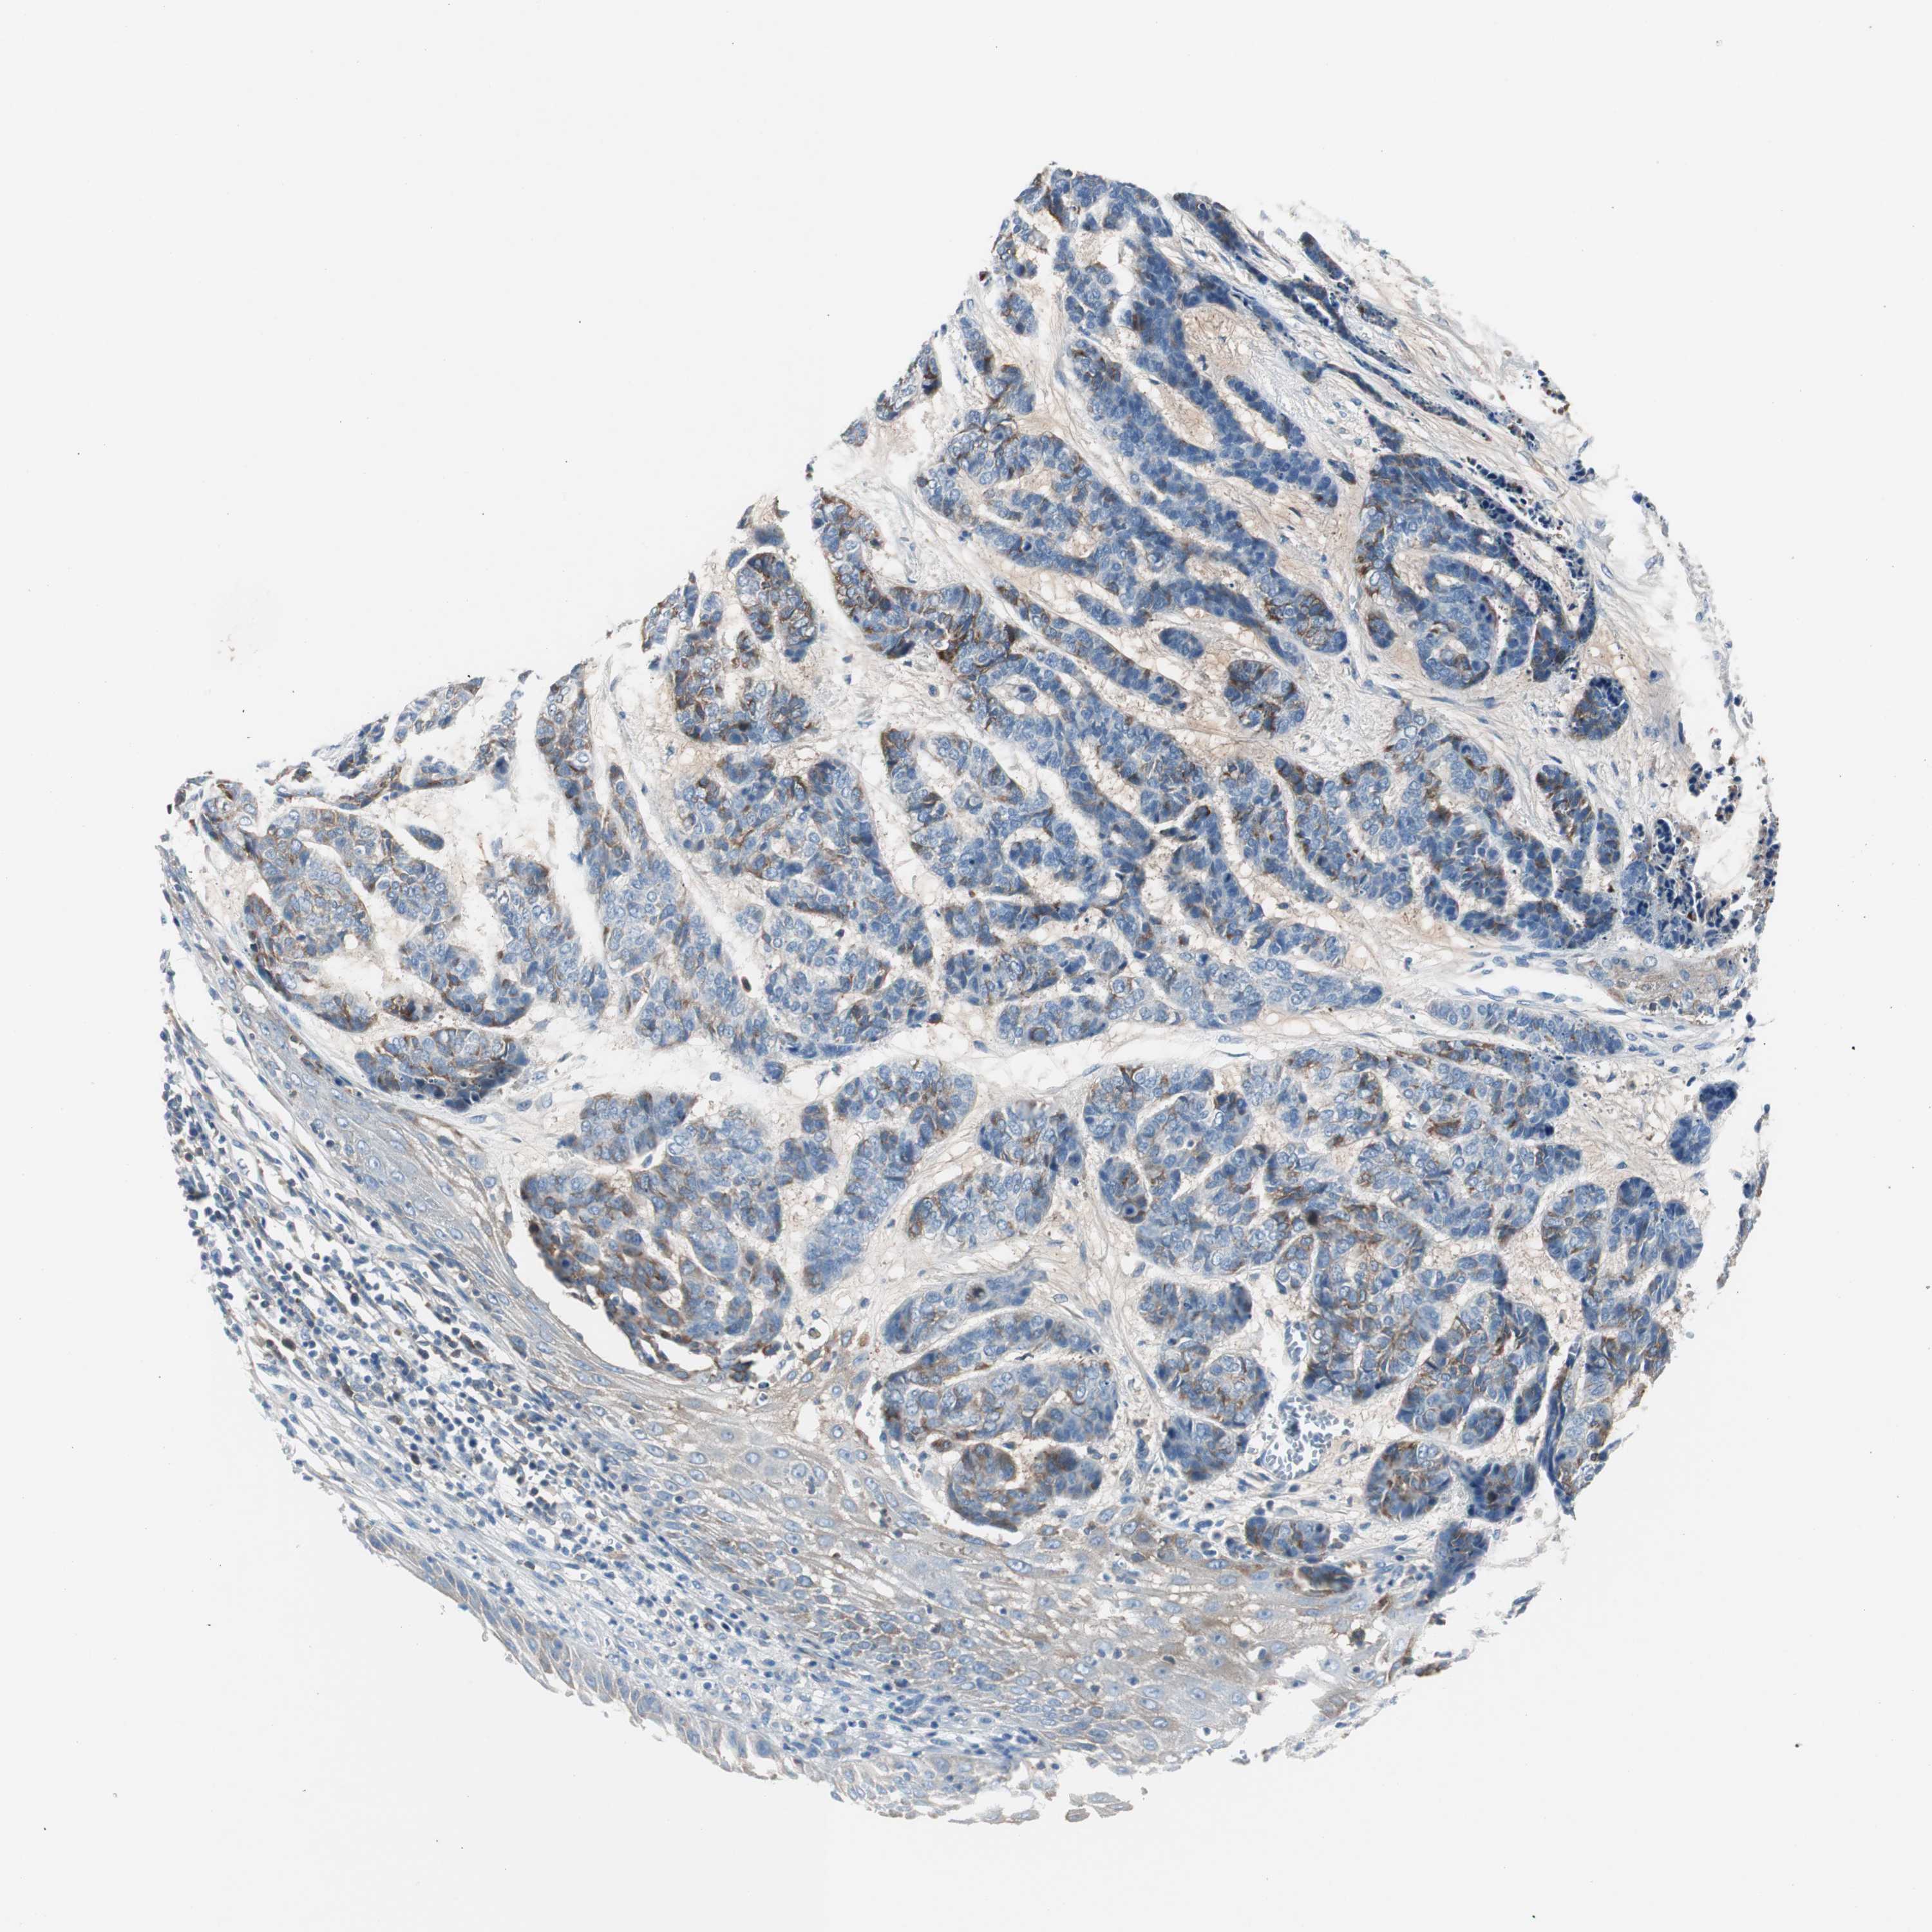

SKIN CANCER - Protein expressioni

A mouse-over function shows sample information and annotation data. Click on an image to view it in a full screen mode. Samples can be filtered based on level of antibody staining by selecting one or several of the following categories: high, medium, low and not detected. The assay and annotation is described here.

Antibody stainingi

Antibody staining in the annotated cell types in the current human tissue is reported as not detected, low, medium, or high, based on conventional immunohistochemistry profiling in selected tissues. This score is based on the combination of the staining intensity and fraction of stained cells.

Each image is clickable and will lead to virtual microscopy that enables deeper exploration of all samples and also displays staining intensity scores, fraction scores and subcellular localization as well as patient and tissue information for each sample.

Antibody HPA005825

Squamous cell carcinoma, NOS

Basal cell carcinoma